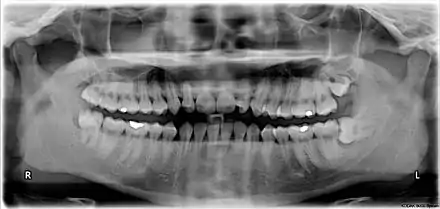

Wisdom teeth in the human mouth for permanent teeth. There are none in deciduous (children's) teeth.

The upper left (picture right) and upper right (picture left) wisdom teeth are distoangularly impacted. The lower left wisdom tooth is horizontally impacted. The lower right wisdom tooth is vertically impacted (unidentifiable in orthopantomogram).